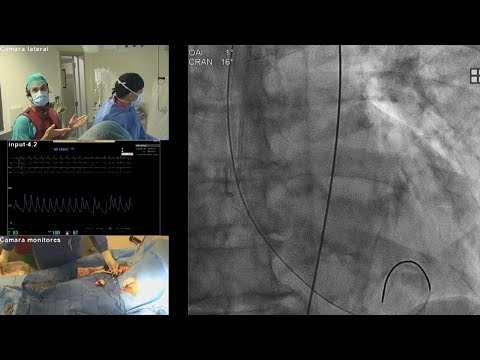

Favaloro Live Case N° 24 - TAVI en Aorta Angulada con Válvula VitaFlow